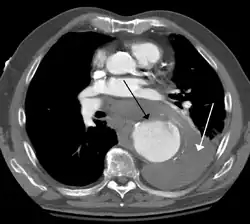

A thoracic aortic aneurysm is an aortic aneurysm that presents primarily in the thorax.

A thoracic aortic aneurysm is the "ballooning" of the upper aspect of the aorta, above the diaphragm. Untreated or unrecognized they can be fatal due to dissection or "popping" of the aneurysm leading to nearly instant death. Thoracic aneurysms are less common than an abdominal aortic aneurysm.[2] However, a syphilitic aneurysm is more likely to be a thoracic aortic aneurysm than an abdominal aortic aneurysm. This condition is commonly treated via a specialized multidisciplinary approach with both vascular surgeons and cardiac surgeons.

Thoracic aortic aneurysm is defined as a cross-sectional diameter exceeding the following cutoff:

- 4.5 cm in the United States[7]

- 4.0 cm in South Korea[8]

A diameter of 3.5 cm is generally considered dilated.[7] However, average values vary with age and size of the reference population, as well as different segments of the aorta.